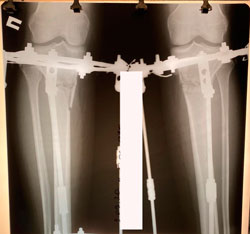

Исходник - 40 лет.

Дата операции - 19.08.2020

image-19-08-20-07-33-1.jpg

image-19-08-20-07-33-7.jpg